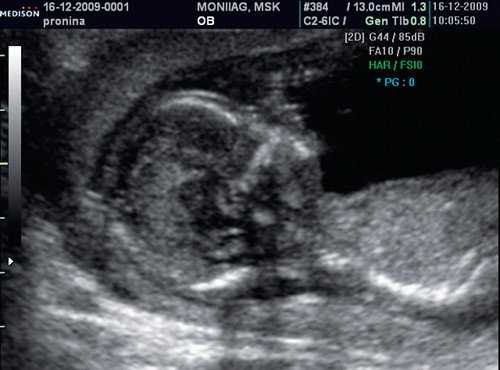

Цель 3D-ультразвукового исследования состоит в создании объемного изображения в отличие от двухмерного метода, создающего плоскостные сечения [6, 11]. Объемная картина получается при сканировании смежных сечений — это объем пространства пирамидальной формы (рис. 3, 4).

Рис. 3. Плод, 31 неделя, 3D-ультразвуковое исследование / Fig. 3. Fetus, 31 weeks, 3D

Рис. 4. Плод, 32 недели, 3D-ультразвуковое исследование / Fig. 4. Fetus, 32 weeks, 3D

Время сканирования в среднем составляет от 3 до 10 с в зависимости от важности объемной информации и требуемого качества изображения.